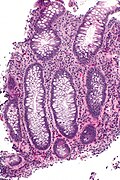

Paneth cell metaplasia and lamina propria eosinophils. H&E stain.

The Paneth cell is characteristic of the small intestine. It is also normal in the cecum, ascending colon and transverse colon.

• Paneth cells should not be in the left colon.[1]

• If you see 'em there it is Paneth cell metaplasia.

Microscopic

Features:

• Supranuclear eosinophilic granules.

DDx:

• Enterochromaffin cells (AKA Kulchitsky cells).

• Subnuclear eosinophilic granules.

• Intraepithelial eosinophils.

• Eosinophils have smaller (~1/2) more intensely red granules.